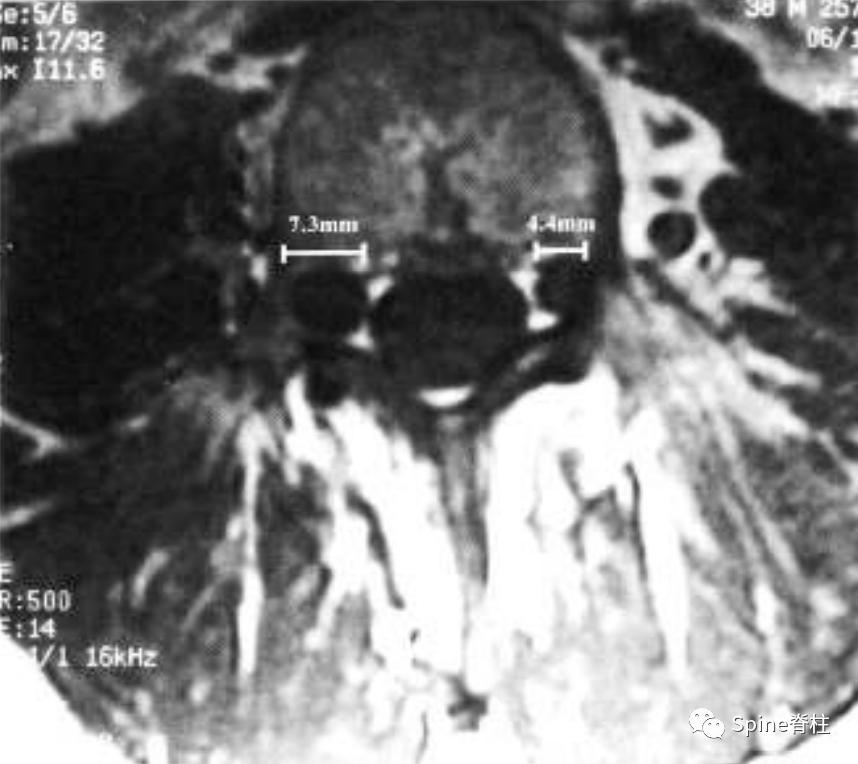

- L5神经根袖直径>6.5mm

测量L5处的最大神经根袖直径 (nerve root sleeve diameter) 。请注意,神经根袖的直径右侧为7.3 mm,左侧为4.5 mm。因此,L5神经根袖的最大值为7.3 mm,这符合次要标准之一。只有当最大值超过6.5 mm时,才满足L5神经根袖直径的次要标准。